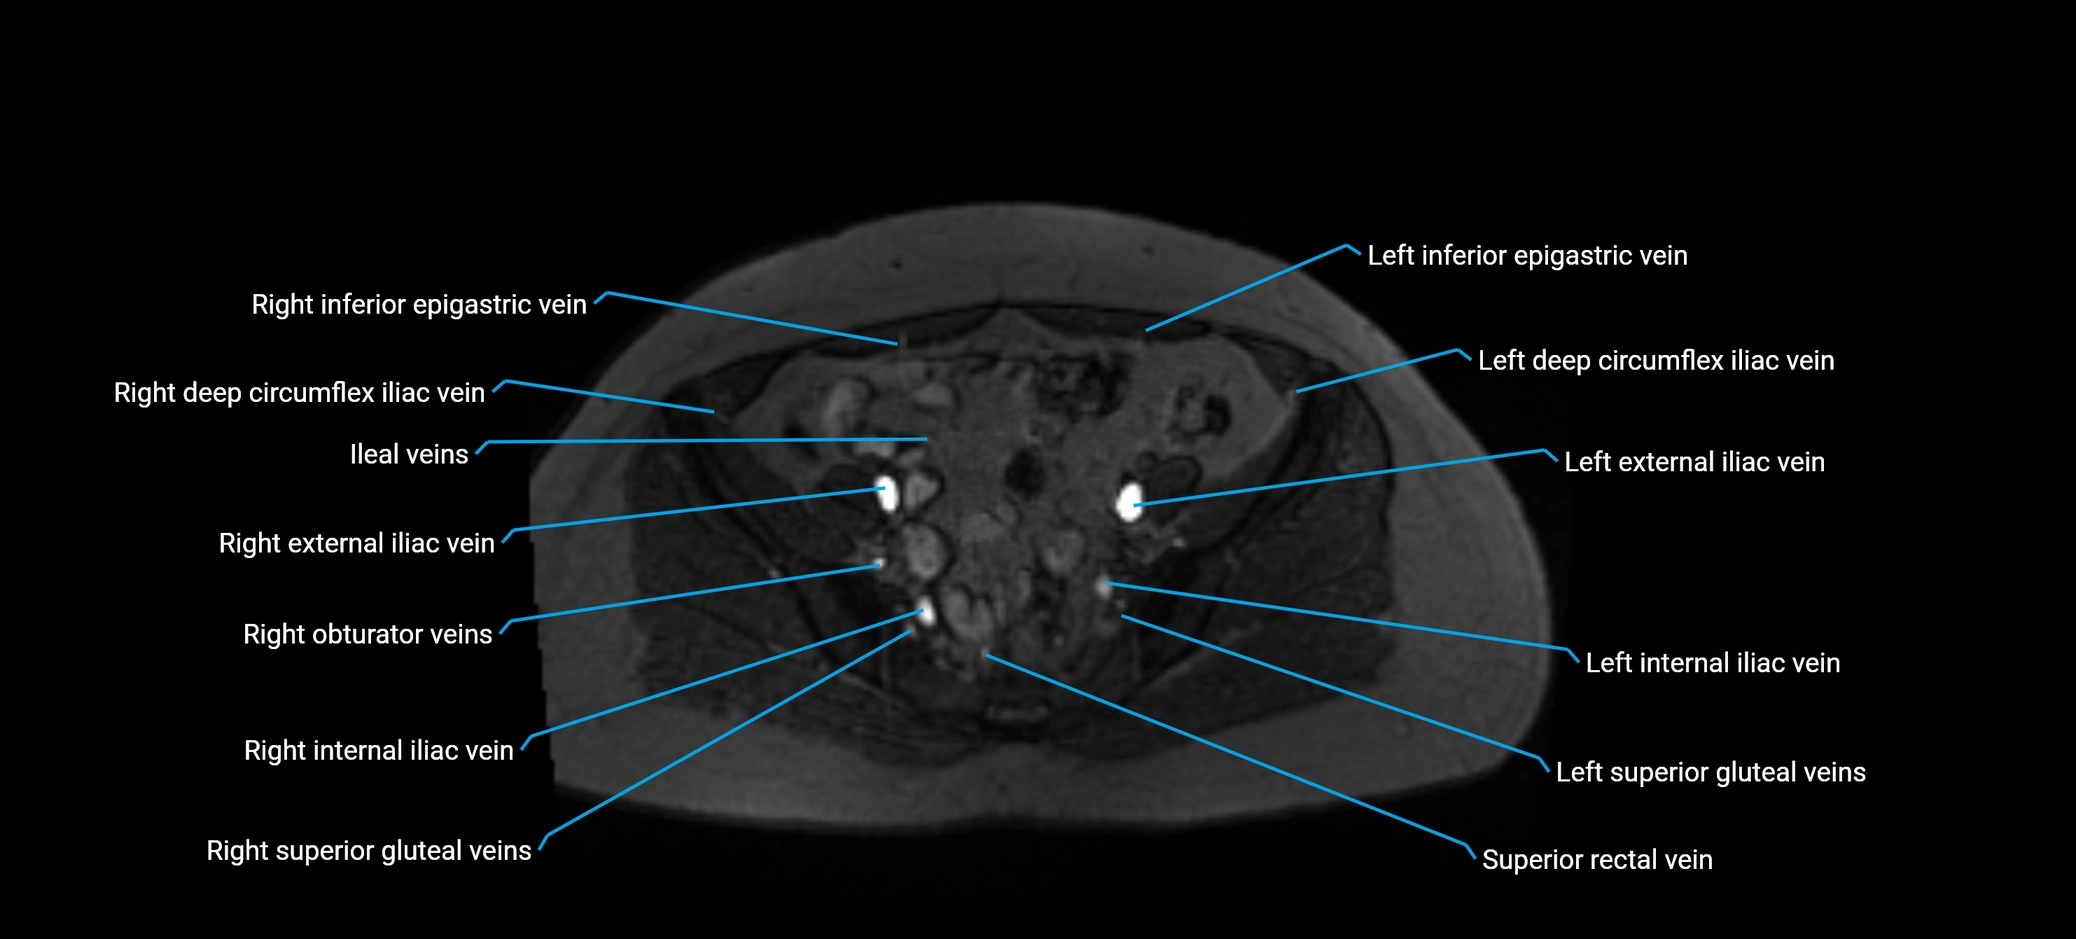

MRI image

image